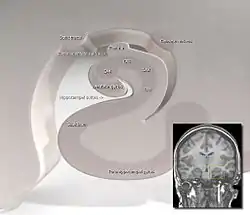

![]() Hippocampus location and regions in a human, coronal plane | |

The hippocampus proper refers to the actual structure of the hippocampus which is made up of three regions or subfields. The subfields CA1, CA2, and CA3 use the initials of cornu Ammonis, an earlier name of the hippocampus.

There are four hippocampal subfields, regions in the hippocampus proper which form a neural circuit called the trisynaptic circuit.